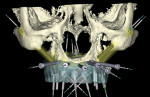

Ten radiopaque markers (gutta percha, Hygenic®, Coltène/Whaledent Group, www.coltene.com) were placed in the maxillary complete denture to prepare the denture for a specific guided- surgery protocol (NobelClinician™ Software, Nobel Biocare USA, LLC, www.nobelbiocare.com).23-30 This protocol uses a dual cone beam computed tomography (CBCT) scan procedure. The first CBCT scan (i-CAT®, Imaging Sciences International Inc., www.imagingsciences.com) was taken with the patient’s dentures in place, and a second CBCT scan was taken of the maxillary complete denture alone. The two scans were exported in Digital Imaging and Communications in Medicine (DICOM) format and loaded into the guided-surgery software, where a 3-dimensional (3-D) virtual working model of the patient was generated (Figure 4 through Figure 7) to enable virtual implant planning to be performed. Because the patient’s denture contained the approved esthetic arrangement of the teeth, the implants could be placed virtually in the most prosthetically favorable position.

The finalized virtual implant plan (Figure 8 through Figure 12) consisted of two 10-mm implants and one 13-mm implant in the maxillary anterior region, which engaged the cortical bone at the inferior border of the nasal cavity. The plan called for two 18-mm implants to be placed in the pterygomaxillary31,32 region at an approximately 45-degree angle to the occlusal plane. These pterygomaxillary implants would provide posterior support for the restoration and eliminate a posterior cantilever.33-36 In order to shorten the span between the three anterior and two posterior implants, three zygoma implants were planned on the pre-surgica lcomputer model to transect through the sinus cavity and engage the zygoma bone. All implants in the virtual planning were external-connection regular-platform implants (Brånemark® System, Nobel Biocare).